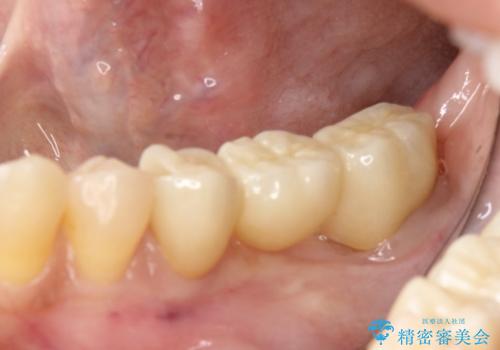

部分矯正してからオールセラミックブリッジ

その後ブリッジの製作を行いました。

セラミック治療の注意事項(リスク・副作用など)

- 天然歯を削ります

- 硬い素材は天然歯を傷つけてしまう場合があります

- かみ合わせや歯ぎしりが強すぎる方はセラミックが割れてしまう可能性があります